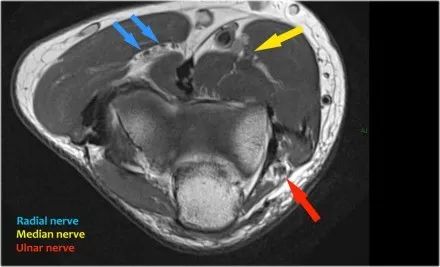

在研究韧带时,尤其是UCL,始终使用轴向图像。如果你看内侧上髁,你会发现后束是一个薄的结构(蓝色箭头)。注意在肘管内的尺神经。

后束形成肘管隧道的地板。支持带覆盖肘管。请注意,前束更厚(白色箭头)。您可以看到前韧带和后韧带之间的区别,即使它们形成一条韧带。走向远端,我们会看到它们合并在一起以附着于崇高的结节。